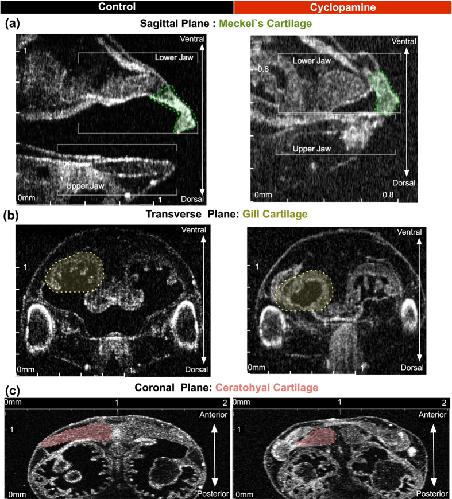

Analysis of Craniocardiac Malformations in Xenopus using Optical Coherence Tomography., Deniz E,Jonas S,Hooper M,N Griffin J,Choma MA,Khokha MK, Sci Rep. February 14, 2017; 7:2045-2322.